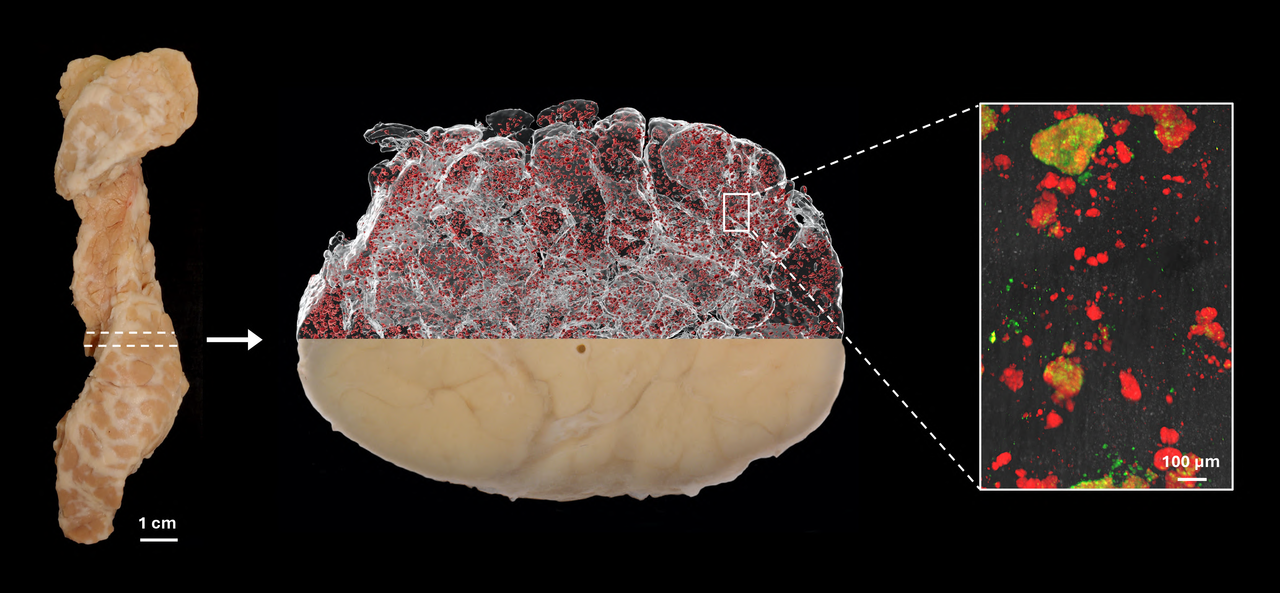

Since the islets of Langerhans make up only a few percent of the pancreas, even though they occur in such large numbers, they have historically been very difficult to study directly within the pancreas. In most cases, researchers have had to study tissue sections that only provide a 2D image of a very small part of the organ. Now, Umeå researchers have used optical 3D techniques in which different cell-types can be marked with fluorescently- coloured antibodies.

"By dividing the entire organ into smaller parts, we enable the antibodies to get where they need to go. Since we know where each piece comes from, we can then, after scanning the different parts individually, ‘reassemble’ the entire pancreas again using computer software. This allows us to perform a plethora of calculations and study which cell-types are present, as well as where they are located in 3D space, as we know the 3D coordinates, their volume, shape and other parameters for each and every stained object in the entire organ.”

Illustrationen visar hur en hel bukspottkörtel (t.v.) från en avliden donator kan färgas in med antikroppar för olika celltyper och avbildas med optisk projektionstomografi (i mitten, Insulinfärgade öar i rött). Den kan sedan studeras i högre upplösning med ljusfältsmikroskopi (t.h.). Det röda är insulin och det gröna glukagon.